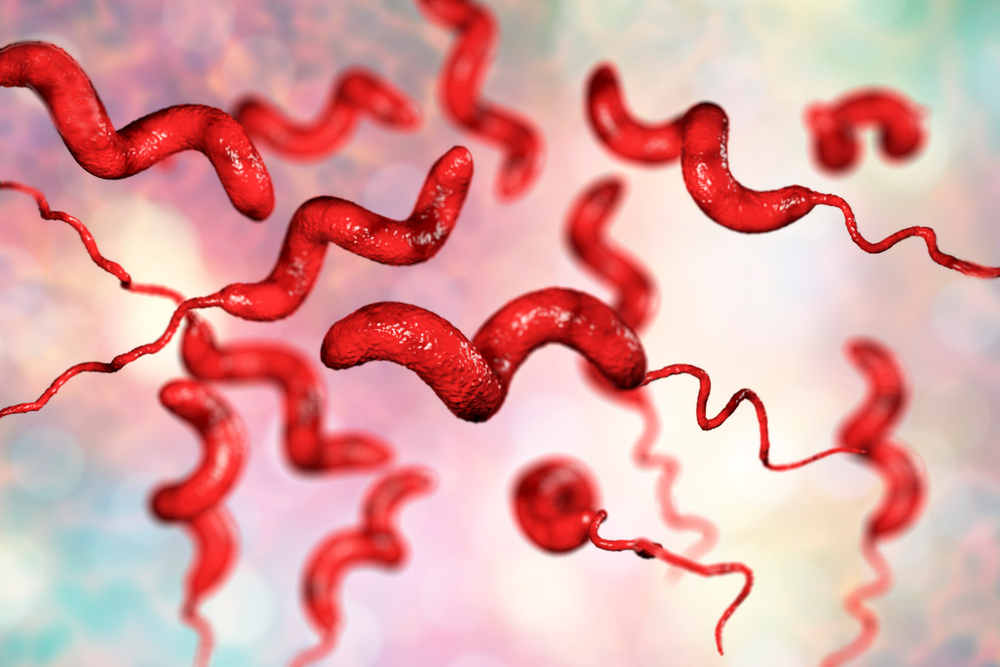

Кампилобактер фетус: патогенез и инфекции